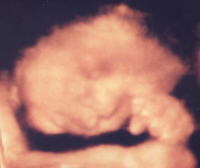

< 3D超音波画像例 >